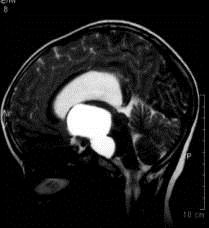

问题 病历摘要:??患者女性,6岁,半年来感觉视力模糊,近10天出现反复头痛,间有恶心呕吐,精神转差,查体:神志清楚,身高90cm,体重25Kg,血压90/55mmHg,右眼视力4.6,左眼视力4.8,双侧视乳头水肿,颈软,伸舌居中,四肢肌张力正常,肌力5级,双侧Babinski征(-)。 入院检查头部MRI,如图所示,诊断有可能是?

选项 A.垂体腺瘤 B.生殖细胞瘤 C.颅咽管瘤 D.视神经胶质瘤 E.蛛网膜囊肿 F.鞍结节脑膜瘤 G.脑积水

答案 CG